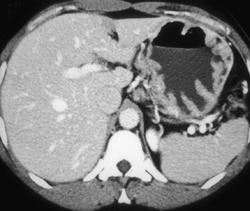

Diagnosis

Carcinomatosis